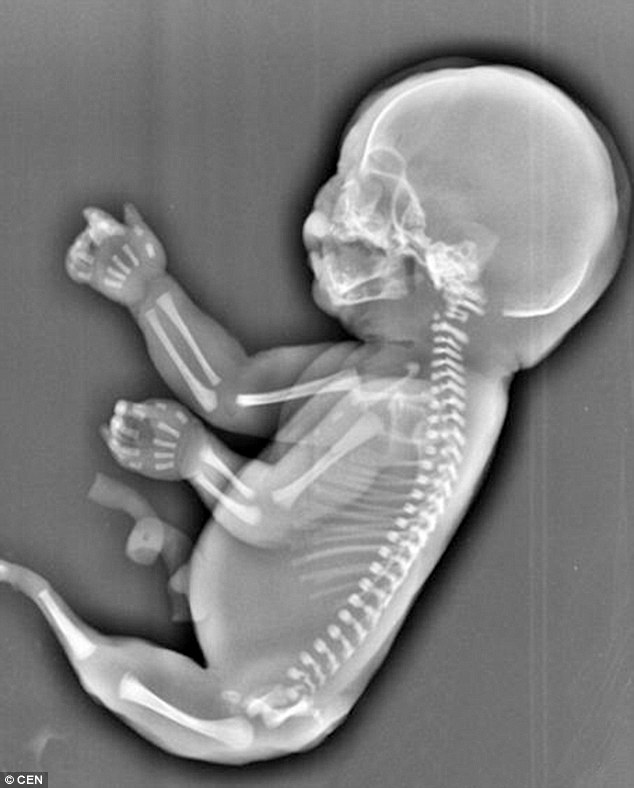

Wu, care era însărcinată în șase luni, a aflat de la doctor că bebelușul său suferă de ”sindromul sirenă”, o afecțiune extrem de rară care apare o dată la 100.000 de nașteri. Sindromul face ca picioarele fetusului să nu se dezvolte separat, ci lipite, semănând cu o coadă de pește. Mai mult, micuțul nu avea vezică urinară, iar ficatul era dezvoltat doar parțial, astfel că bebelușul ar fi trăit doar câteva ore după naștere.

Cu inima grea, tânăra a decis să facă un avort chiar dacă era în luna a șasea de sarcină.